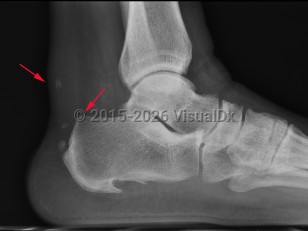

Haglund deformity is enlargement of the posterosuperior tuberosity of calcaneus. Retrocalcaneal bursitis is inflammation of the space between the anterior aspect of Achilles tendon and posterior aspect of calcaneus.